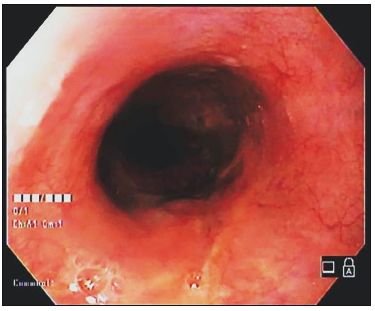

Paciente varón de 56 años, que consultó por pirosis y disfagia, indicándose la realización de una videoendoscopia digestiva alta (VEDA). Se observó en el tercio inferior esofágico una lesión elevada, erosionada, con un tamaño estimado de 20 mm, subpediculada y de aspecto subepitelial (Figura 1). Presentaba una importante dureza al tacto con el fórceps de biopsia. Se realizó una tomografía computada multislice (TCMS) de tórax, observando la lesión en la pared del tercio inferior esofágico, hipodensa y homogénea, sin compromiso del mediastino ni de órganos vecinos (Figura 2).

Figura 1.

Endoscópicamente suelen ser tumores sésiles, de superficie blanquecina y con mucosa respetada, aunque pueden estar erosionados o incluso ulcerados, como en nuestro caso.9